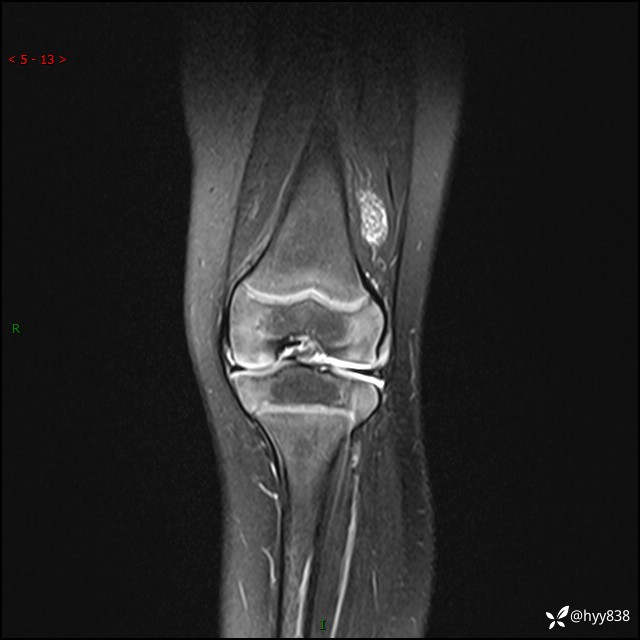

主诉:左下肢跛行1月

现病史:患儿1月前无明显诱因出现左下肢跛行,伴左膝关节红肿,无发热、咳嗽、恶心、呕吐等症,于当地医院就诊行X线片未提示异常,今至我院门诊就诊,门诊医师拟“跛行待查”收入院。 病后,患儿精神、食欲可,睡眠欠安,大小便通畅,体力体重无明显下降。

左膝MRI平扫